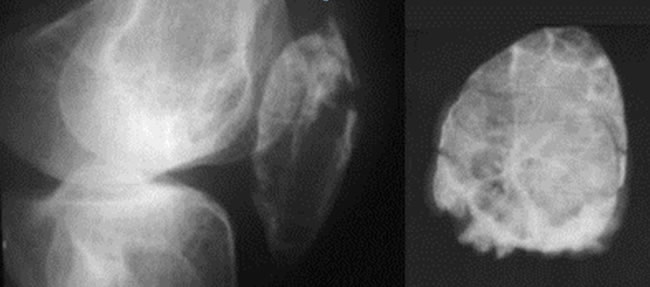

Tumeurs à cellules géantes calmes

Limites nettes, condensées, Cloisons.

Aspect en nid d'abeilles

Cloisons de refend intratumorales.

Trabéculation.

Tumeur à cellules géantes active

Limites imprécises.

Corticales soufflées.

Tumeurs à cellules géantes Agressives

Destruction corticale.

Atteinte des parties molles.

Fracture.

La tumeur à cellules géantes bénigne peut envahir les parties molles

Intérêt du scanner ou de l'IRM

Pour le diagnostique radiologique de bénignité devant une destruction corticale d'une tumeur agressive.

Persistance d'un reliquat périostique limitant l'atteinte des parties molles.

Tumeur agressive